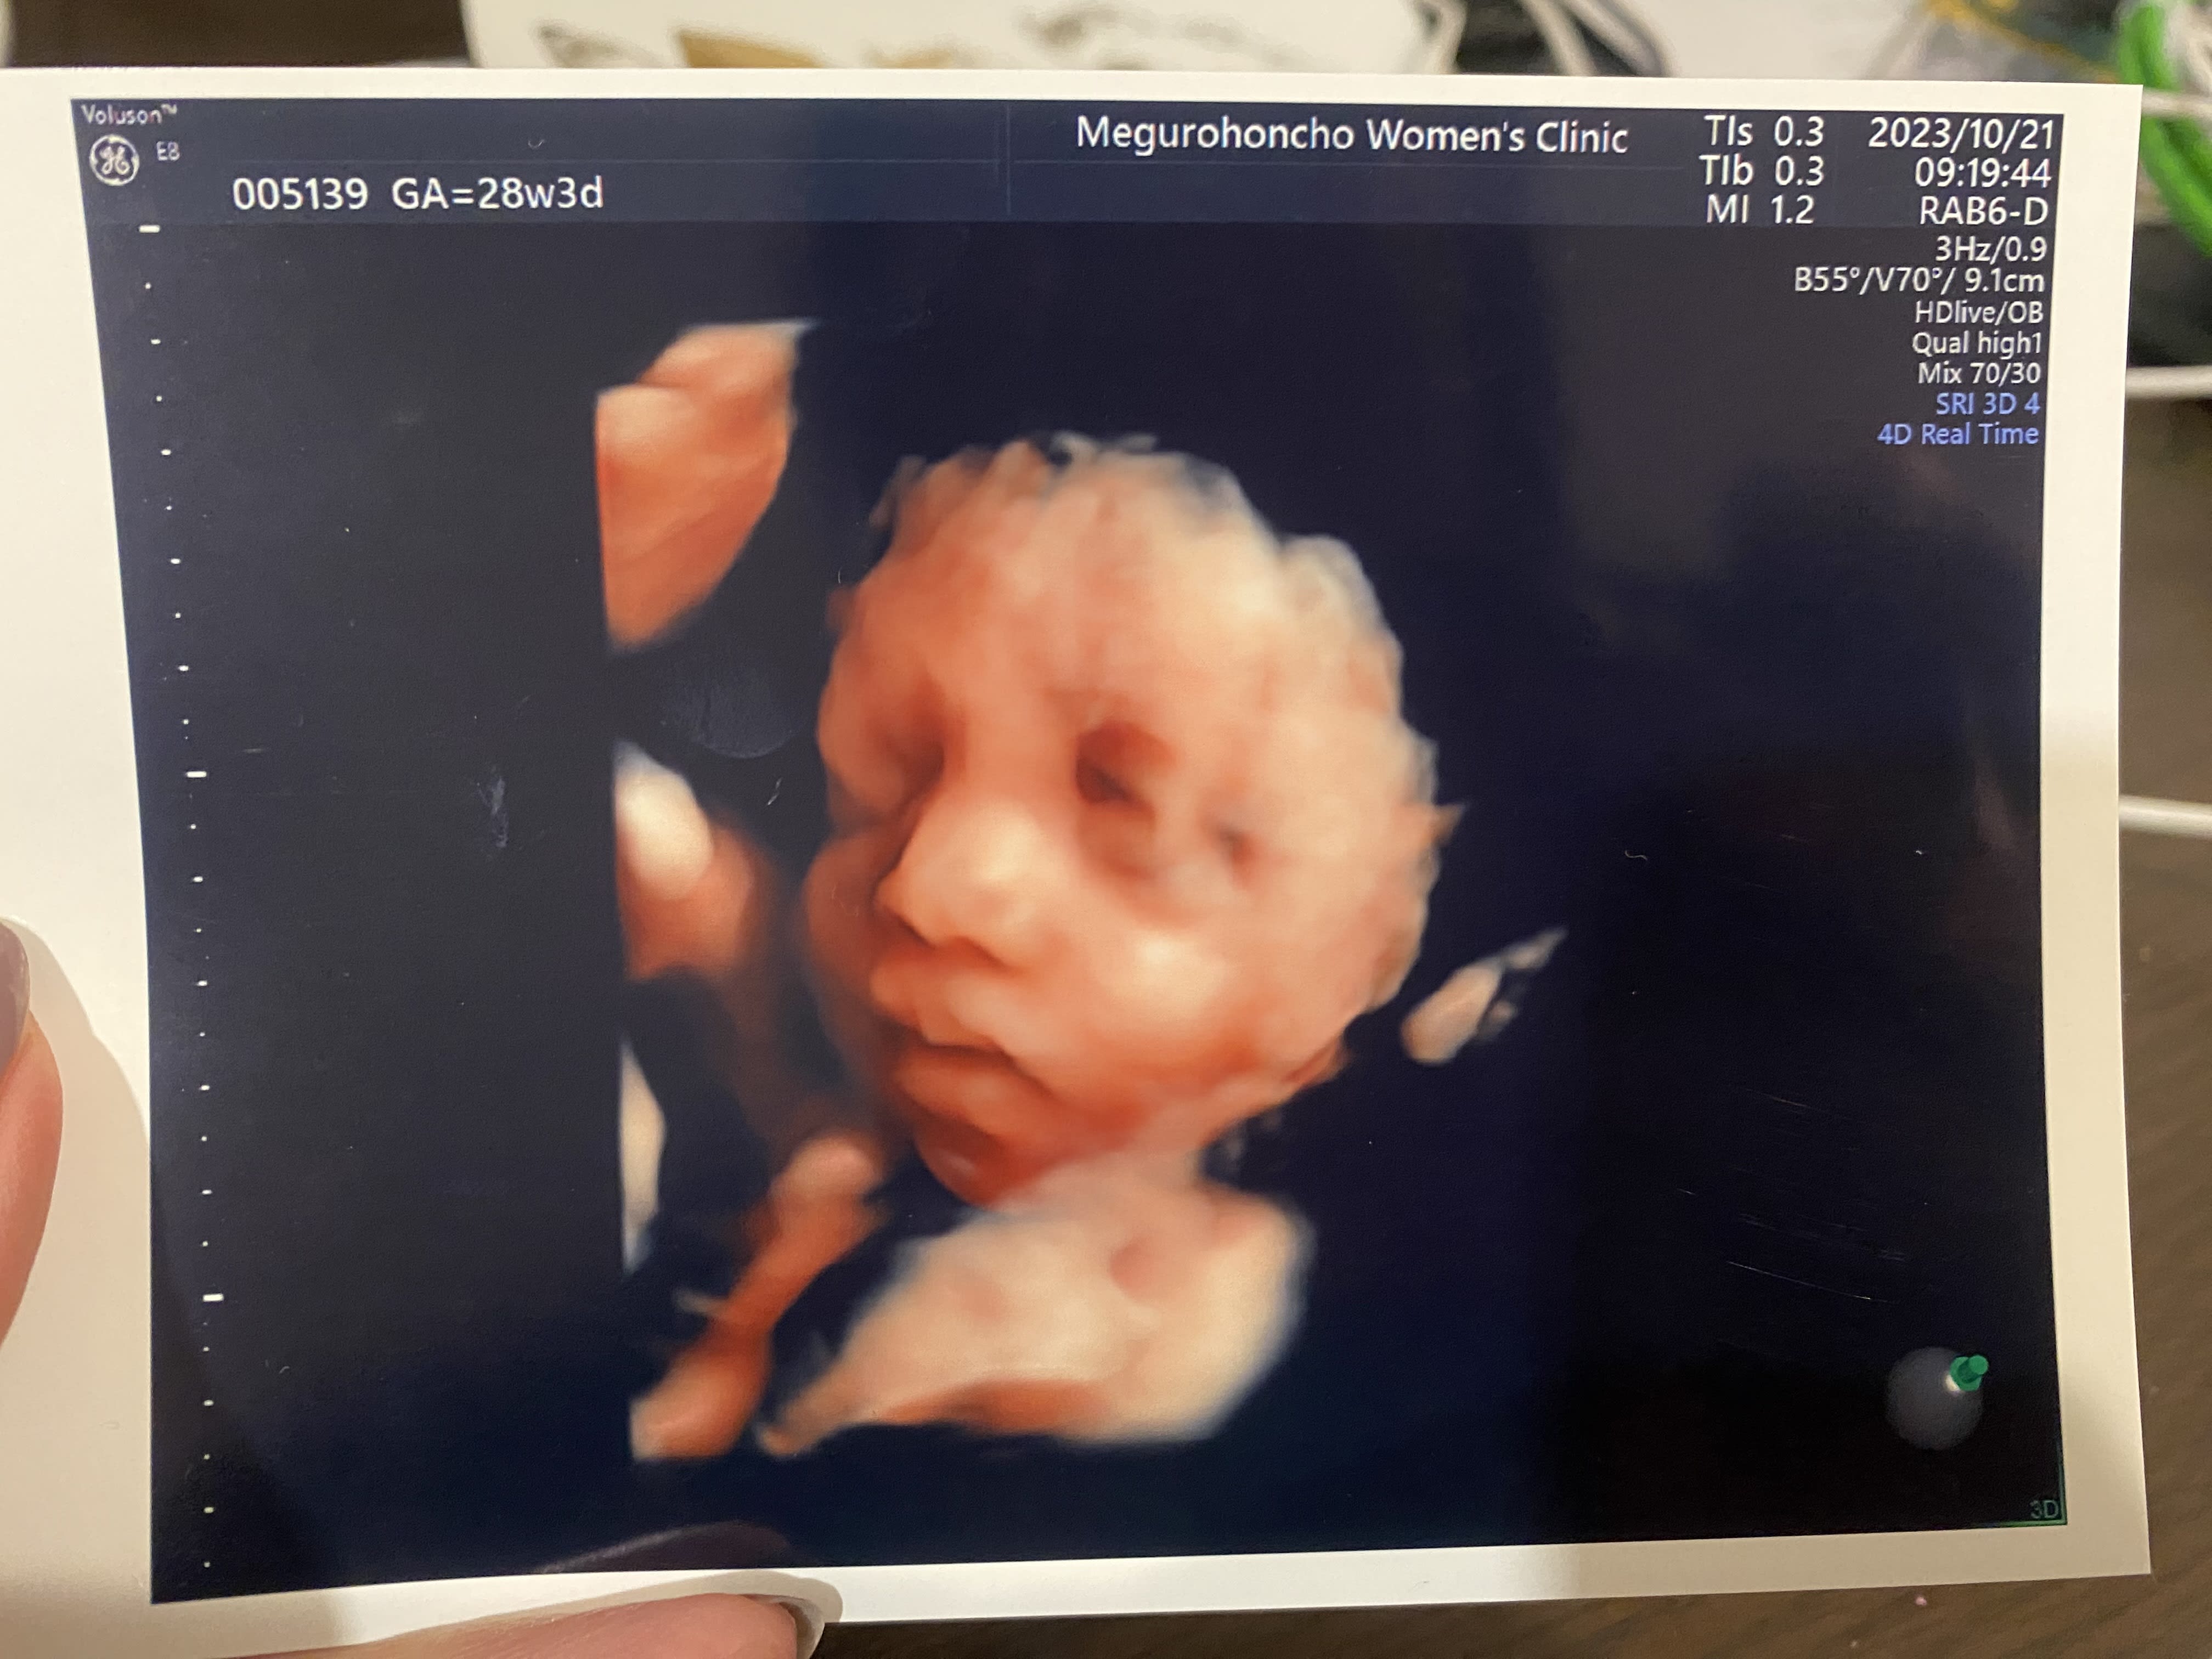

28週の4Dエコー写真。 可愛い顔がしっかりみれて嬉しかったなぁ。 頬っぺたもふっくらしてきて、元気に育ってそうでよかった。

21 Oct 2023